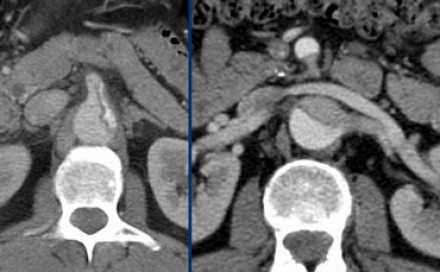

Диссекция абдоминальных артерий

![17]()

- При распространении патологического процесса диссекция может достигать уровня почечных артерий, чревного ствола и передней мезентариальной артерий.

- Истинный просвет вовлекает в патологический процесс чревный ствол, переднюю мезентариальную и правую почечную артерию.

- Просвет левой почечной артерии сужается при увеличении ложного просвета.

- Нарушение перфузии органов обусловлено двумя механизмами:

- 1-статический — распространение диссекции непосредственно в просвет артерии. Хирургическое лечение стентирование.

- 2-динамический — ухудшение прохождения сосуда за счет наличия в просвете сосуда отслоенного слоя.

- При оценке распространенности диссекции обратите внимание на извитость и кальцификацию подвздошных артерий, что важно для эндохирургов.

- Слева представлено прогрессирование диссекции до уровня чревного ствола, в просвете которого определяется ложный просвет, что значительно ухудшает перфузию органов.

- Справа представлен пример вовлечения в патологической процесс передней мезентариальной и почечной артерии.